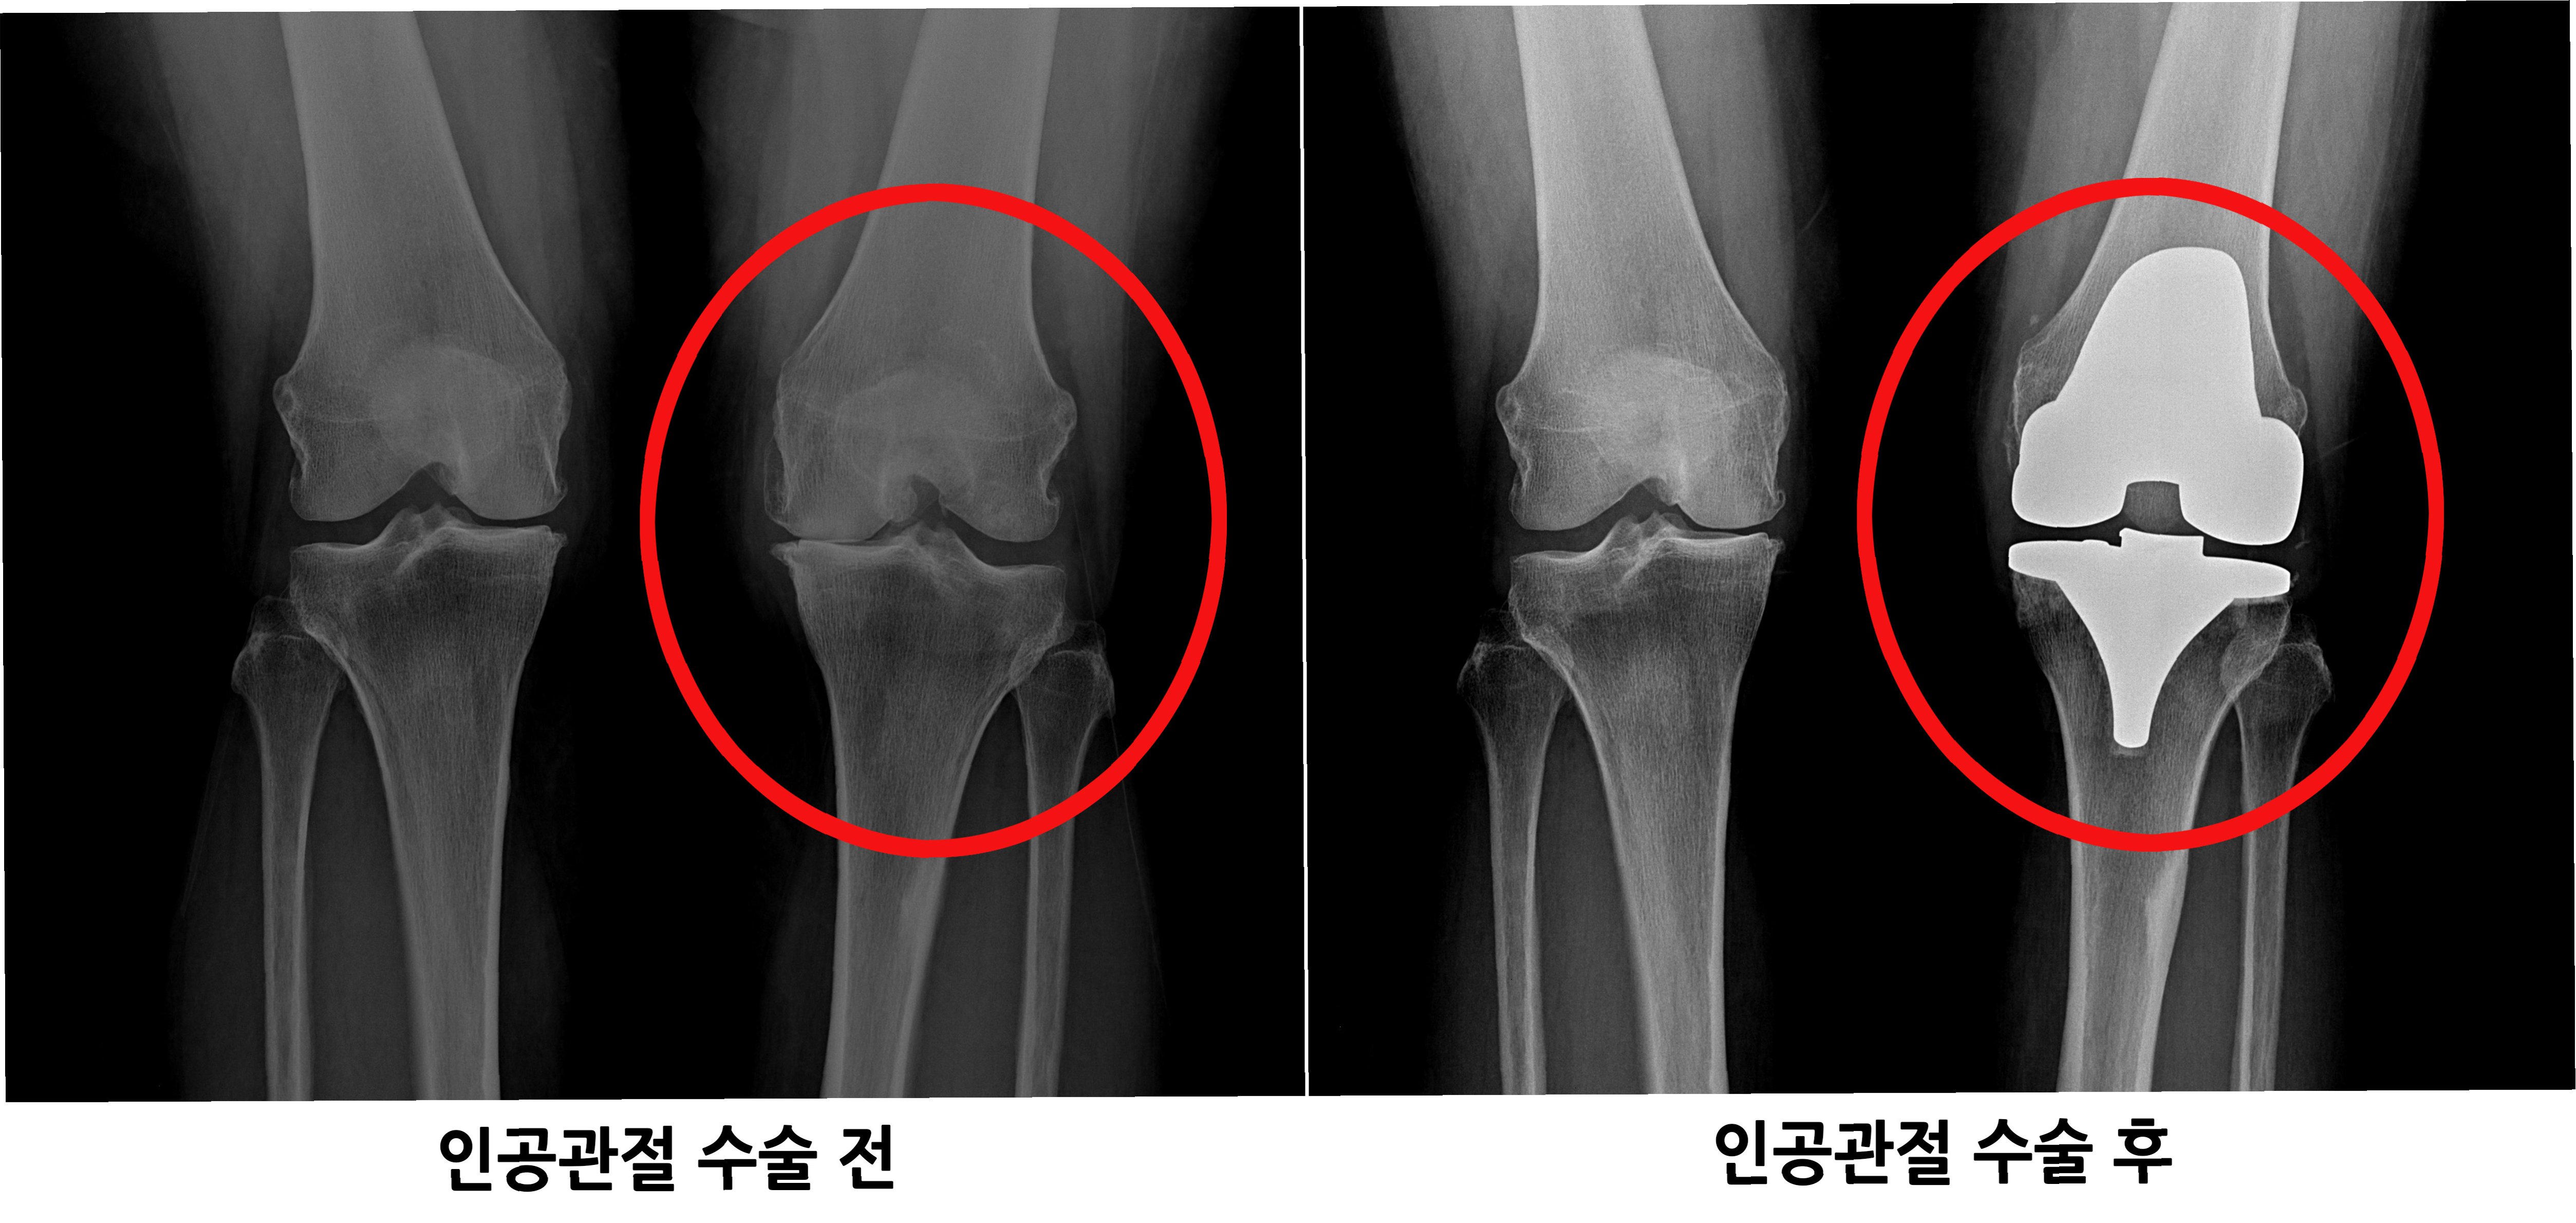

관절은 우리 몸의 움직임을 가능하게 하는 중요한 부분입니다. 하지만 관절 연골이 손상되거나 닳아 없어지면 극심한 통증과 함께 일상생활에 큰 불편함을 겪게 됩니다. 이러한 경우, 인공관절수술은 삶의 질을 향상시키는 효과적인 치료 방법이 될 수 있습니다. 인공관절수술은 손상된 관절을 인공관절로 대체하여 통증을 완화하고 관절의 기능을 회복시키는 것을 목표로 합니다. 수술 후에는 보다 자유롭고 활동적인 생활을 누릴 수 있으며, 긍정적인 심리적 변화도 기대할 수 있습니다. 인공관절수술은 단순히 통증을 없애는 것을 넘어, 환자가 건강하고 행복한 삶을 되찾도록 돕는 중요한 과정입니다.

인공관절수술은 다양한 관절 질환에 적용될 수 있습니다. 대표적인 질환으로는 퇴행성 관절염, 류마티스 관절염, 외상 후 관절염 등이 있습니다.

1. 퇴행성 관절염: 관절 연골이 닳아 뼈와 뼈가 직접 닿아 통증과 염증을 유발하는 질환입니다.

인공관절수술은 일반적으로 손상된 관절 부위를 절개하고, 손상된 뼈와 연골을 제거한 후 인공관절을 삽입하는 방식으로 진행됩니다. 수술 시간은 관절 부위, 수술 방법, 환자의 상태에 따라 다르지만, 대개 1~3시간 정도 소요됩니다. 수술 후에는 통증 관리와 함께 조기 재활 운동을 시작하여 관절의 기능 회복을 돕습니다. 초기에는 보행 보조기구(목발, 보행기 등)를 사용하며, 점차적으로 사용 빈도를 줄여나갑니다. 재활 운동은 관절의 가동 범위를 늘리고 근력을 강화하여 일상생활 복귀를 돕는 데 매우 중요합니다. 회복 기간은 개인의 상태, 수술 방법, 재활 노력에 따라 다르지만, 일반적으로 수술 후 3~6개월 이내에 일상생활로의 복귀를 목표로 합니다. 꾸준한 재활과 관리를 통해 건강한 관절 기능을 회복하고 오랫동안 유지할 수 있습니다.